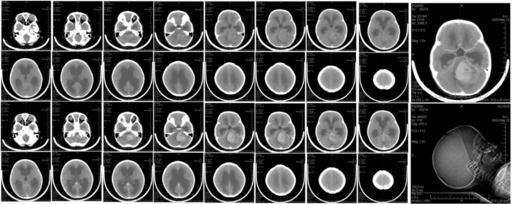

MAKE A MEME View Large Image CT brain scan of child with medulloblastoma and resulting hydrocephalus.jpg Six-year-old girl with medulloblastoma Medulloblastoma Neuroradiology

View Original:CT brain scan of child with medulloblastoma and resulting hydrocephalus.jpg (5290x2105)

Keywords: CT brain scan of child with medulloblastoma and resulting hydrocephalus.jpg Six-year-old girl with medulloblastoma Medulloblastoma Neuroradiology